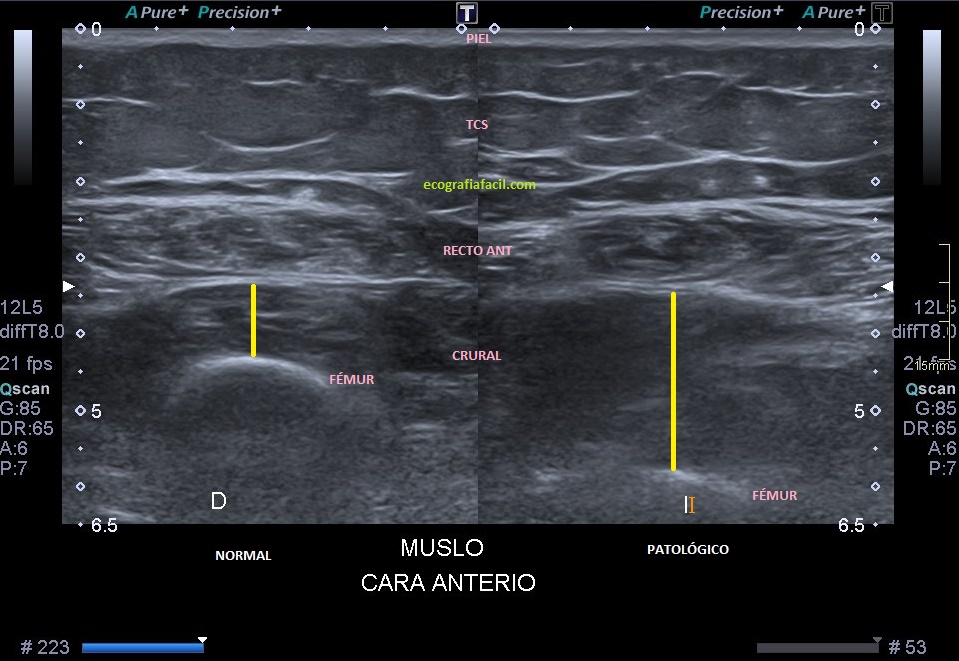

En la ecografía lo primero que veo al realizar la exploración en el corte axial del tercio medio es una llamativa diferencia de la ecoarquitectura del tercio medio del fémur afectado. En este caso lo que se observa a ojo de buen cubero es aumento del volumen antero posterior del Músculo Crural con respecto al Recto Anterior. Ese aumento de calibre es en todo el recorrido del fémur anterior, con lo que la afectación es desde proximal a distal del músculo citado anteriormente.

Ecogénicamente se ve un recto anterior hipoecogénico, como tiene que ser, el Crural es un músculo de aspecto heterogéneo, grande, sin vascularización con el Doppler Color ni con el Doppler Power.

In ultrasound, the first thing I see when performing the exploration in the axial section of the middle third is a striking difference of the ecoarchitecture of the middle third of the affected femur. In this case, what is observed an increase in the anteriorvolume of the Crural Muscle with respect to the Anterior Rectus. This increase in caliber is throughout the course of the anterior femur, with which the affectation is from proximal to distal of the muscle previously spoken.

Echogenically, a hypoechoic anterior rectum is seen, as it must be, the Crural is a muscle with a heterogeneous, large appearance, without vascularization with Color Doppler or with Power Doppler.

En la primera imagen encuentro ya los cambios referidos en el párrafo anterior. Inmediatamente en la imagen 2, comparativa de ambas estructuras, patológica y normal.La imagen 3 es una imagen correlacionada de RM, potenciada en T1 para que veas el mismo corte con dos técnicas diferentes, ambas en corte axial.